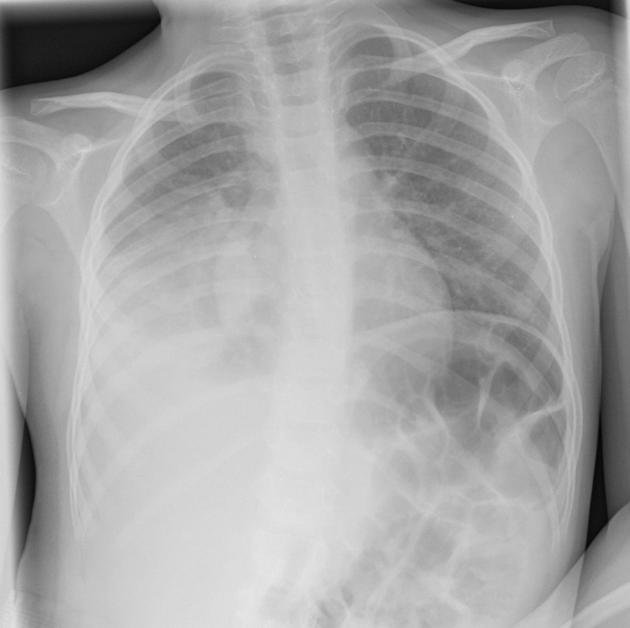

Acute alveolar filling may cause a ____ lung pattern resembling ill-defined pulmonary nodules (usally more severe _____ and fading periherally.

mottled

centrally

Radiographic findings with an alveolor lung pattern can be:

(Alveolar patterns tend to change rapidly over short periods of time)